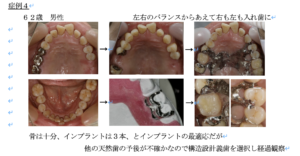

症例4